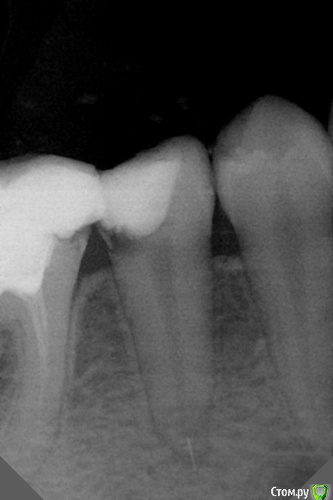

dr.Dre Опубликовано 20 октября, 2016 Поделиться Опубликовано 20 октября, 2016 Добрый вечер,периодонтит 45 зуба ,сломал новый Mtwo 15 ,подскажите уважаемые коллеги как выйти с данной ситуации реально ли извлечь инструмент и как? Ссылка на комментарий

vse32 Опубликовано 20 октября, 2016 Поделиться Опубликовано 20 октября, 2016 Оставляйте, но по теме - сначала измеряйте рд. Что бы не ломать инструменты в апикальном сужении. Ну и для нормального формирования апикального упора. Ссылка на комментарий

krokomot Опубликовано 20 октября, 2016 Поделиться Опубликовано 20 октября, 2016 надо было стенку восстановить, а то никакого герметизма. 1 Ссылка на комментарий

dr.Dre Опубликовано 20 октября, 2016 Автор Поделиться Опубликовано 20 октября, 2016 Он очистке не препятствует. При нормальной обработке все будет хорошо.не протолкну ли в мягкие ткани при обробке? Ссылка на комментарий

dr.Dre Опубликовано 21 октября, 2016 Автор Поделиться Опубликовано 21 октября, 2016 "мягкие ткани"-это куда , простите?извините неправильно написал в кость Ссылка на комментарий